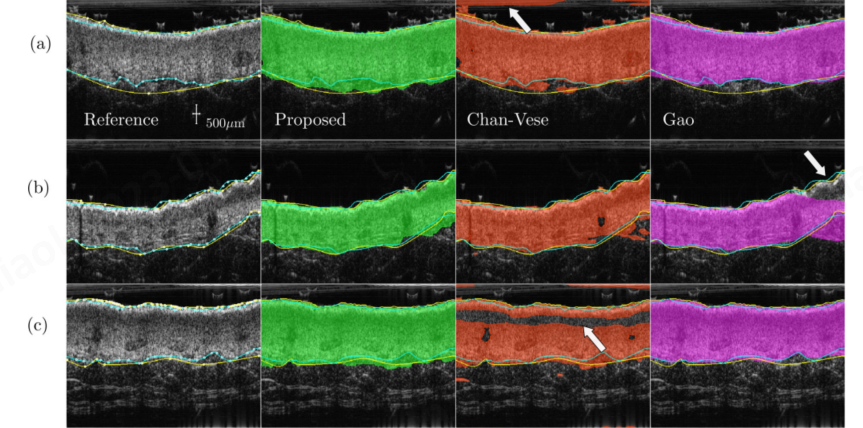

比较了三种分割真皮层的方法

Chan-Vese模型,基于区域的主动轮廓模型;

Gao method 基于Sobel边缘算子的主动轮廓,引入了一种新的双曲线方案,不能自动初始化;

一种多重损失水平集分割算法,结合纹理准则、表皮mask和水平连续性的几何约束,将表皮和真皮层联合分割(Proposed)。